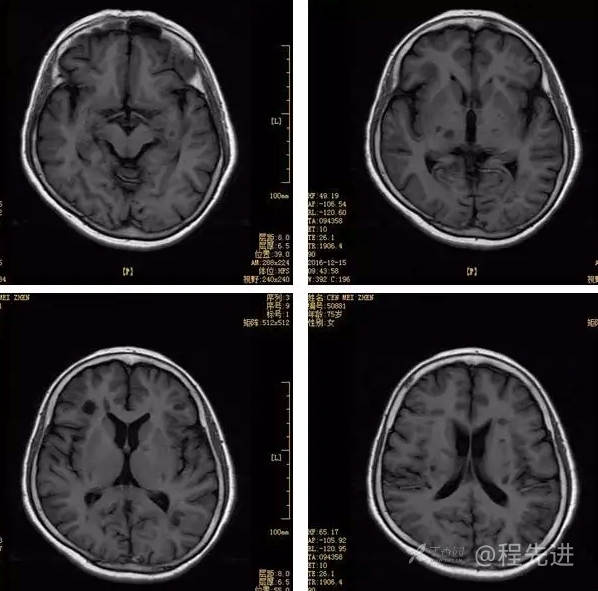

3月特别精彩病例|头晕伴左侧肢体乏力、行走不稳1周【结果已公布】

患者性别:女

患者年龄:75岁

简要病史:头晕伴左侧肢体乏力、行走不稳1周。否认高血压、脑梗塞、肝炎、糖尿病、肺结核病史。否认疫区疫水接触史。